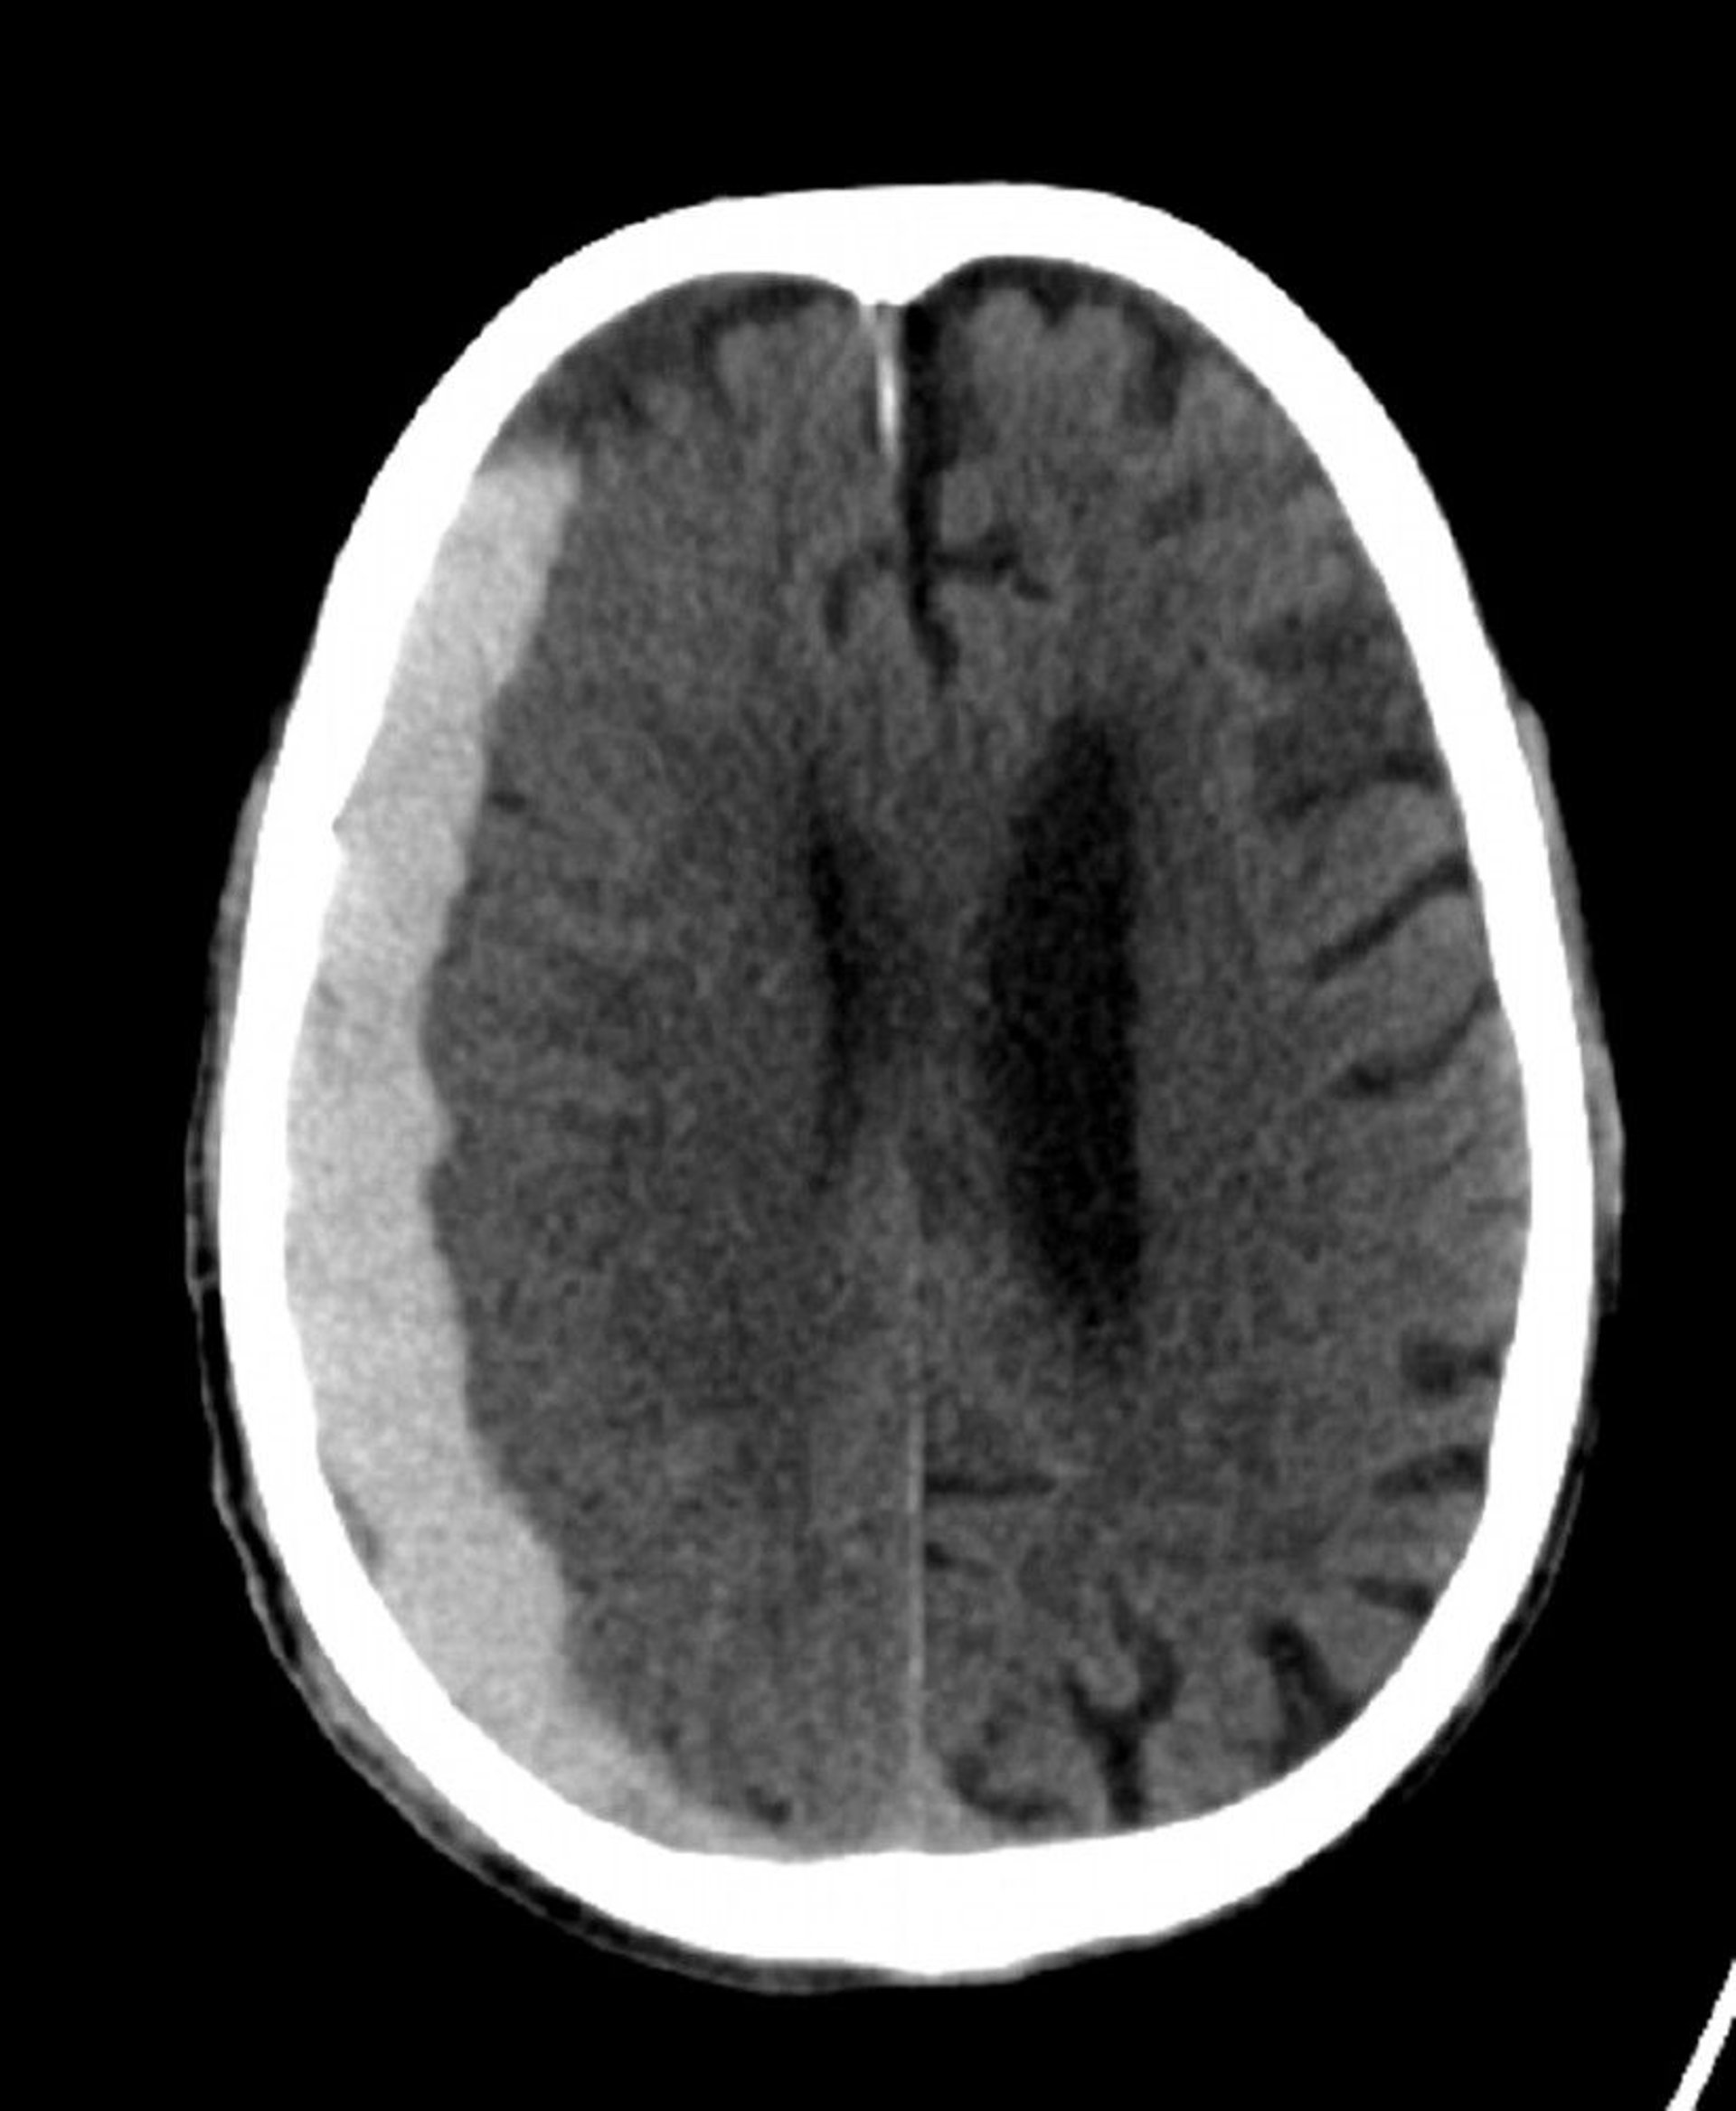

Subdural Hemorrhage (CT)

Classic crescent-shaped hyperdensity extending across suture lines.

© 2017 Elliot K. Fishman, MD.